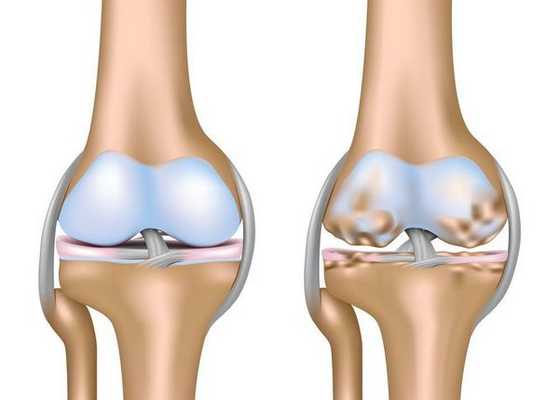

Артроз коленного сустава (гонартроз) — это прогрессирующее хроническое заболевание коленных суставов с повреждением, истончением и разрушением его хрящевой части (суставные поверхности бедренной и большеберцовой костей), а также поражением субхондральной кости. [2] [5] [16] Доказано исследованиями (артроскопия и МРТ), что помимо поражения суставного хряща в процесс вовлекаются мениски и синовиальная оболочка. Гонартроз — одна из самых распространенных ортопедических патологий. [4] [6] [9] [22] Существуют его синонимы — остеоартроз (ОА), деформирующий артроз. Заболевание является важной социально-экономической проблемой, так как широко распространено и значительно ухудшает качество жизни больных из-за постоянного болевого синдрома и, кроме того, становится причиной высокой инвалидизации. [15] [27]

До середины восьмидесятых годов прошлого века не было унифицированного определения заболевания. Только к 1995 году комитетом по остеоартрозу Американского колледжа ревматологии заболевание было охарактеризовано как результат действия механического и биологического факторов, приводящих к дисбалансу между процессами деградации и синтеза внеклеточного матрикса суставного хряща. [11] [19] В итоге происходит его разволокнение и дегенерация, образуются трещины, остеосклероз и уплотнение кортикального слоя субхондральной кости, растут остеофиты и формируются субхондральные кисты. [12] [29]

При артрозе (остеоартрозе) кроме прогрессивного разрушения хряща, потери его эластичности и амортизирующих свойств, в процесс постепенно вовлекаются кости. [7] [29] Под нагрузкой возникают заострения по краям (экзостозы), которые по ошибке считают "отложениями солей" — при классическом артрозе никакого отложения солей не происходит. Прогрессируя, артроз продолжает «съедать» хрящ. Затем деформируется кость, там происходит образование кист, поражаются все структуры сустава, и нога искривляется. [11] [17]

Первая стадия заболевания характеризуется первичными изменениями в гиалиновом хряще. [12] [18] Костные структуры не затрагиваются. Во внутрикостных сосудах и капиллярах нарушается кровоснабжение. Становится сухой поверхность хряща, и он утрачивает свою гладкость. Если заболевание сопровождается постоянным напряженным синовитом, то развивается киста Бейкера (грыжевое выпячивание капсулы сустава подколенной области). [15] После значительной нагрузки на сустав возникают тупые боли. Возможна небольшая отечность, которая проходит после отдыха. Деформации нет.

На второй стадии хрящевая прослойка резко истончается, а местами и вовсе отсутствует. [22] Появляются остеофиты по краям суставных поверхностей. Изменяются качественные и количественные характеристики синовиальной жидкости сустава — она становится гуще, более вязкой, что приводит к ухудшению питающих и смазывающих свойств. [14] [16] Боли более продолжительные и интенсивные, часто при движении появляется хруст. Отмечается незначительное или умеренное ограничение движений и небольшая деформация сустава. Прием анальгетиков помогает снять болевой синдром.

Отсутствие хряща на большинстве поражённых участков, выраженный склероз (уплотнение) кости, множество остеофитов и резкое сужение или отсутствие суставной щели. [8] [15] Боли практически постоянные, походка нарушена. Подвижность резко ограничена, заметна деформация сустава. Препараты НПВС, физиопроцедуры и другие стандартные методы лечения артроза коленного сустава неэффективны. [11]